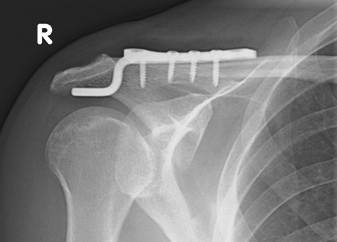

AC Luxation Typ Rockwood 3 vor Versorgung mit Balser Hakenplatte (Clavicular Hook Plate)